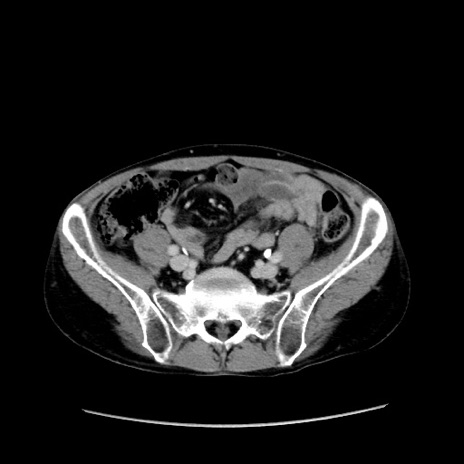

症例37(横断像)

【症例】40歳代 男性

【主訴】腹痛

【現病歴】4時間ほど前に電車に乗車中に臍部上より腹痛出現。徐々に増悪し起立困難となり、救急外来受診。生ものは数日食べていない。今朝お雑煮を食べた。

【身体所見】BT 36.8℃、BP 117/84mmHg、HR 91/min、SpO2 97%、苦悶様、腹部:臍上部広範囲圧痛あり、反跳痛±

【データ】WBC 8100、CRP 0.03